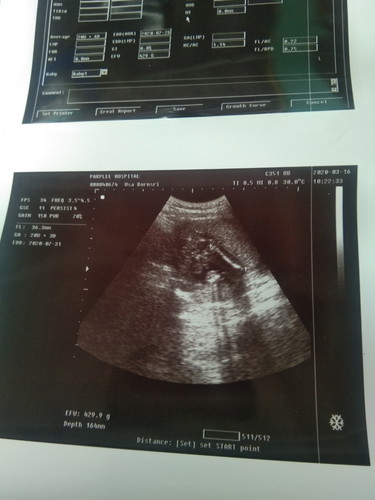

แม่ดูไม่ออกเลยจ้าว่าส่วนไหนเป็นส่วนไหน แต่หมอบอกน้องเป็นผช. 21 w